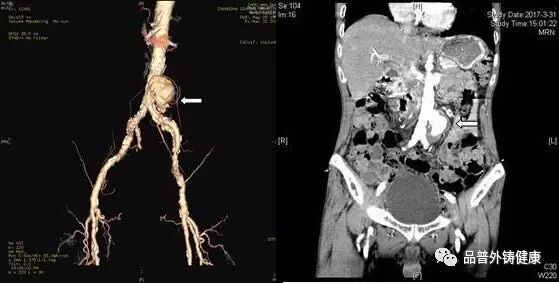

75岁的周老先生半年前出现咳嗽、咳痰、胸痛等不适,一直以为是感冒,没有引起重视,间断治疗半年也不见好转,后辗转来到长沙市中心医院肺科医院就诊,经肺部CT、痰培养等一系列检查下来,确定是肺空洞型结核,马上开始抗结核治疗。治疗没几天,患者出现腹痛,再次行腹部CT检查发现腹主动脉瘤。请普外科的血管外科周杰斌副主任医师会诊并完善主动脉CTA检查后,周教授当即决定转科手术治疗。

患者由肺科医院转入我科,经术前评估,患者为高龄,合并慢性阻塞性肺疾病、肺部感染及房颤,加之肺结核的影响,肺功能很差,不能耐受全麻手术。周教授在仔细阅片后认为假性动脉瘤破口位于左侧肾动脉开口下方约6cm,紧邻双侧髂总动脉,周围组织结构不清,存在炎性病灶可能,结合患者病史,不排除结核性血管炎,血管置换存在感染风险,决定局部麻醉下行腹主动脉支架腔内隔绝术,用最小的创伤解除患者假性动脉瘤随时可能破裂出血的风险。手术由周杰斌、曾赟裘副主任医师配合完成,切开皮肤,置入血管鞘、导丝及导管,血管造影,置入覆膜支架隔绝瘤体,再次造影确认等这一系列步骤一气呵成,一个小时便顺利完成手术,术后患者腹痛症状消失。